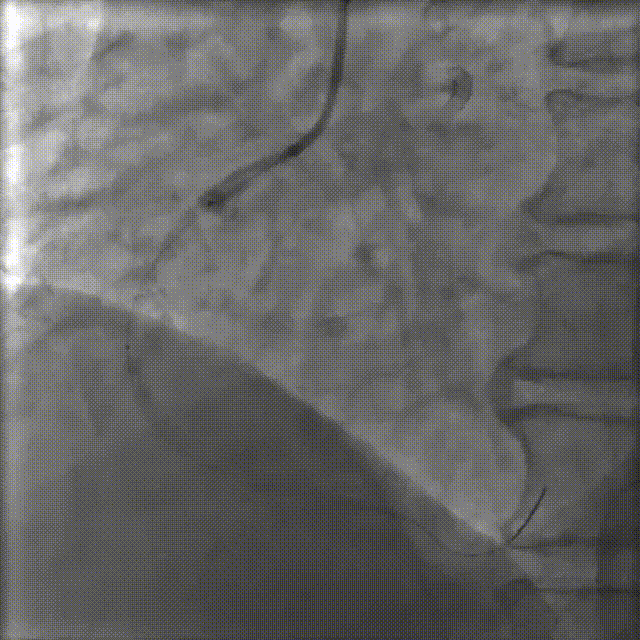

LCX—OCT术前检查

回旋支近段,远段ISR,最狭窄平均直径1.26mm;管腔面积 1.26mm²;以纤维斑块为主。